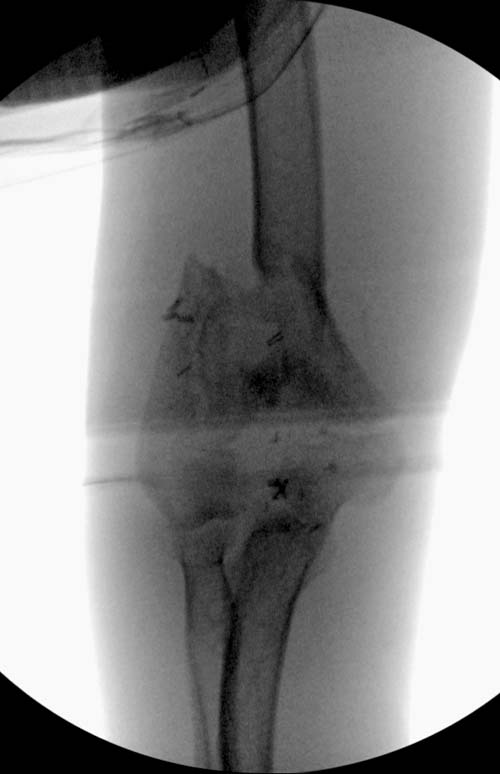

остаться до конца лечения, начал изучать язык... Для облегчения

транспортировки на второй день после поступления правая сторона была

фиксирована ретроградным гвоздем.

Теперь по серьезному. Учитывая качество кости и низкий гемоглобин,

периодический гемодиализ и воодушевленный результатом выступлении

Челнокова, вместо пластины решил попробовать гвоздь. Но жесткие FDА

Гвоздь из ретроградного гвоздя DePuy в 15 мм получился немного тоньше,

чем у Российских коллег.

Операция не обошлась без казуса, при подготовке гвоздя произошла ошибка

в расчете. Пришлось коррегигировать по ходу операции, где длинный

дистальный отдел гвоздя срезали во время операции.

А так вроде первый американский опыт прошел удачно. У больного низкий

гемоглобин, который подправили во время операции переливанием крови.

надеюсь, контрагированные мышцы сохранит длину конечности. Контрольный

снимок показал устойчивую фиксацию.